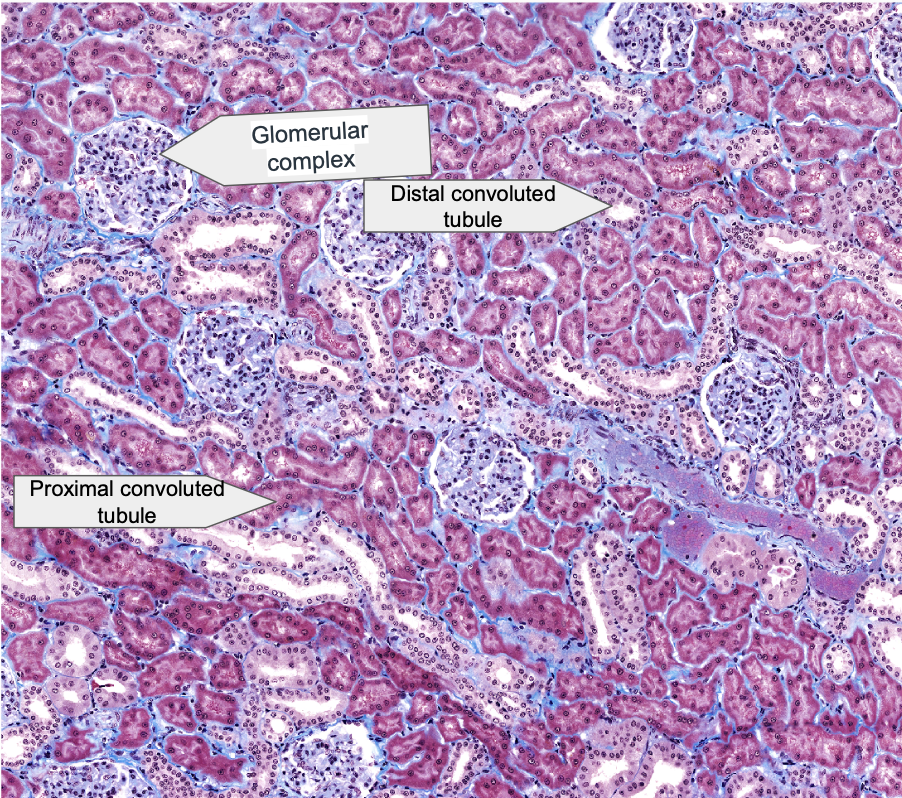

List layers of Kidney (Low magnification view)

High magnification of renal cortex- list different parts